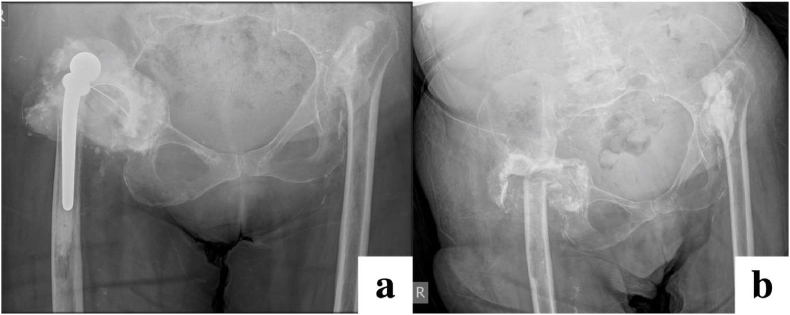

Fig. 7.

Radiographs demonstrating persistent chronic infection and prosthetic right hip dislocation (a), treated with pseudoarthrosis (b). Patient had also previously undergone pseudoarthrosis of the left hip for the same indication.